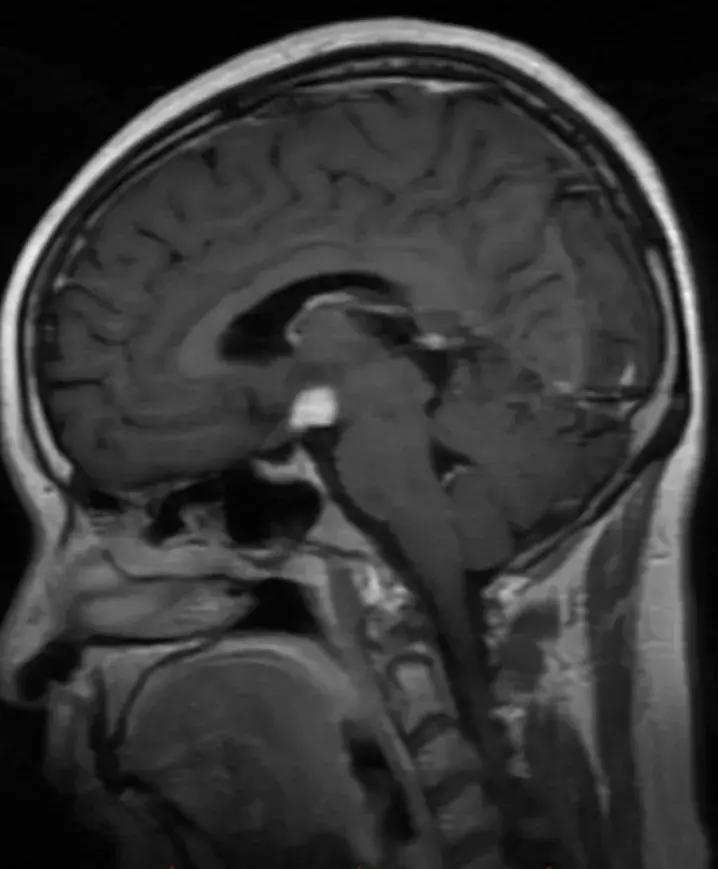

下丘脑见一类圆形异常信号灶,大小约1.6×1.4cm,T2WI呈等略高信号,T1WI呈等信号,DWI呈等信号,增强后明显异常强化,轻度压迫视交叉,FLAR见视交叉及双侧后方视束信号增高。